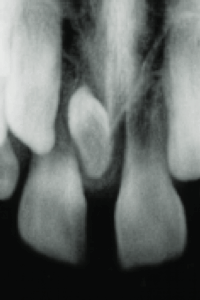

②上顎の真ん中に過剰歯がある(正中過剰埋伏歯)

上顎の左右の中切歯の間やその近傍に位置する、余分な歯(過剰歯)のことで、他の歯の萌出を阻害したり、中切歯の傾きの変化を引き起こして、正中離開を生じさせる原因となることがあります。

頻度としては、研究により0.15~2 %程度という報告があり、男性に多く、10~12歳付近で検出されることが多いです。

↑ 上の前歯の間に小さい余分な歯がある場合があります